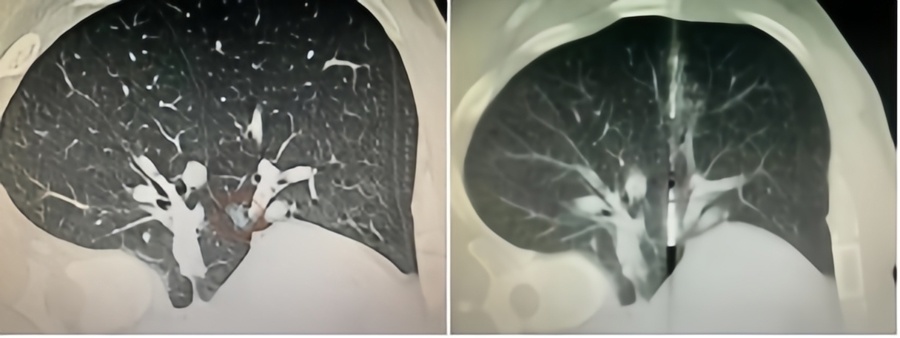

微波针是什么体检发现肺磨玻璃结节,只能随访手术二选一?“超微创”的微波消融,了解一下_https://www.jmylbn.com_新闻资讯_第2张术前影像和术中穿刺消融

术中,手术团队借助CT影像三维定位系统清晰地了解结节的位置、大小、形状以及与周围组织的关系,在这幅精确的 “导航地图”的指引下、结合个人丰富经验,将直径仅1.3毫米的消融针经皮穿刺至核心,在保留安全边界的情况下,通过微波产生的热效应将结节彻底烧灼和消融。整个治疗过程仅用了30分钟左右,术中王女士意识清醒,没有出现任何并发症。术后病理证实为原位腺癌,一周复查显示结节完全消融。